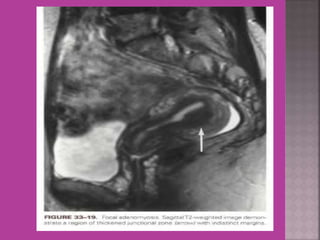

 Adenomyosis---accurate diagnosis.

 MRI is most sensitive for diagnosis of Adenomyosis.